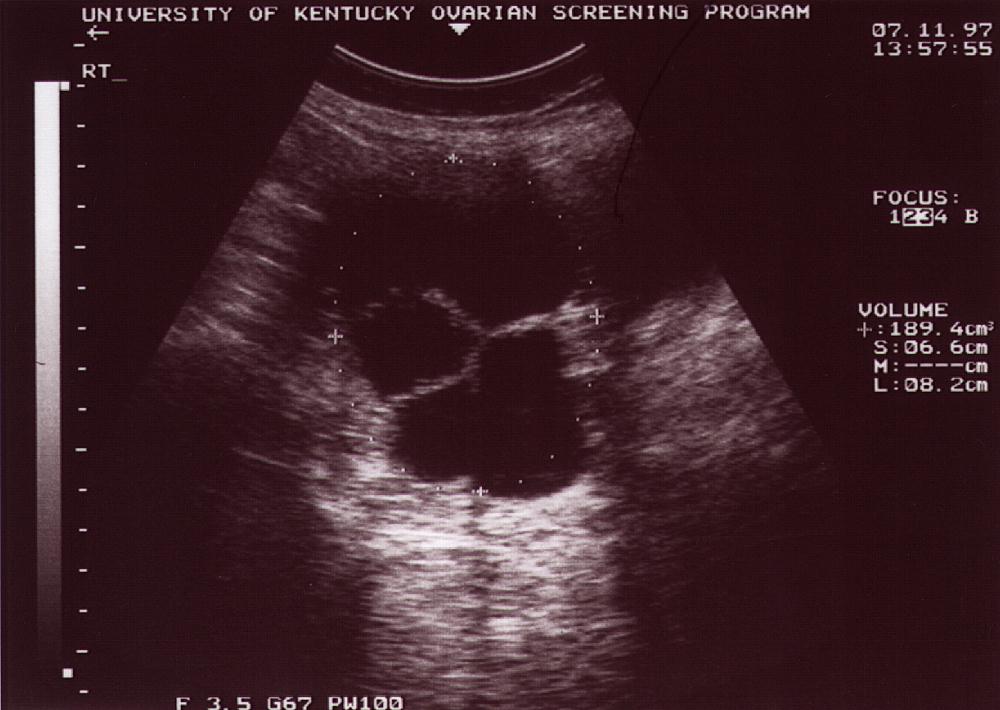

Case H

Case

H

Age at Dx

63

TVS size, cm3

223.1

TVS – cystic

+

TVS – solid

TVS – papillation

TVS – septation

TVS – MI

8

Tumor Stage

IA

Treatment

S

Status

A & W

DX Date

Jul-97

Years Post Dx